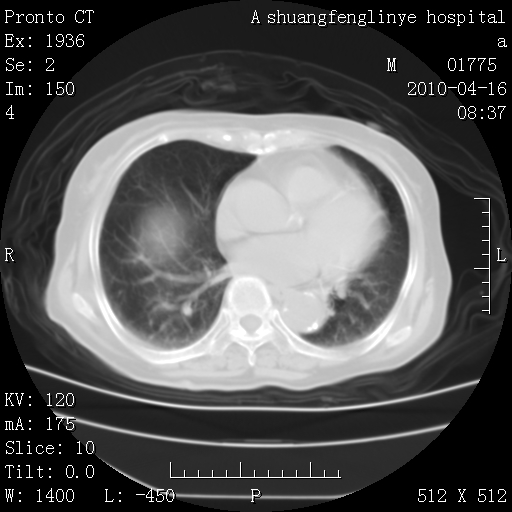

标题: CT25784:咳痰、请会诊!结核? [打印本页]

标题: CT25784:咳痰、请会诊!结核?

考虑左肺上叶增殖灶、纤维灶。

慢支肺气肿,左上陈旧性结核,主动脉冠脉钙化

1)左肺上叶结核(纤维、增殖病灶)。2)冠状动脉及主动脉钙化。

1)左肺上叶结核(纤维、增殖病灶)。2)冠状动脉及主动脉钙化。肺动脉高压